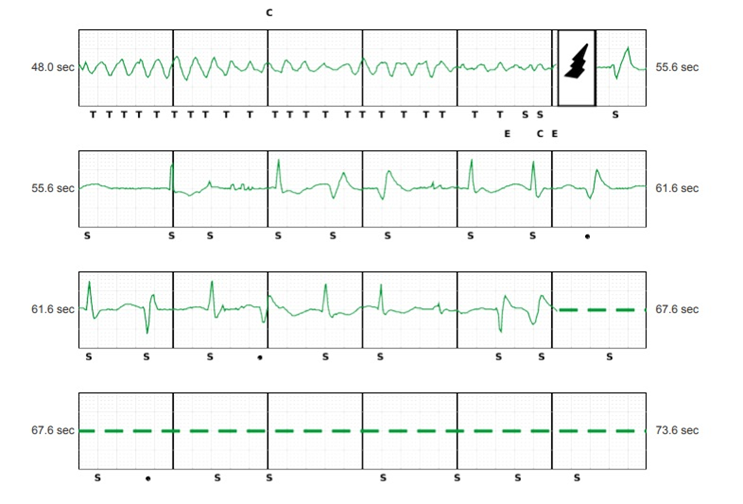

The interrogation of the S-ICD found one arrhythmic event (appropriate electrical shock for VF) preceded by prolonged QT interval (figure 4)

During the hospitalisation, the patient presented another syncope due to a new arrhythmic event despite the absence of any acute trigger (no infection, no ischemia, no electrolyte abnormalities or hormonal imbalance, no QT-prolonging drugs etc) except probably the subclinical inflammation due to the recent Mitra clip intervention (figure 6).

There is an elongated QT interval (not standardized measurement on S-ICD tracings but QT interval longer than half of the RR space) and we can see a PVC that falls on a T wave resulting in ventricular fibrillation. An appropriate choc was delivered by the S-ICD.